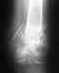

Re: Перелом беровой кости со смещением

Вы не представили рентгенограмм и фото поврежденного отдела, так что не очень ясно, какое конкретно повреждение имеется, и какая именно операция остеосинтеза планируется.